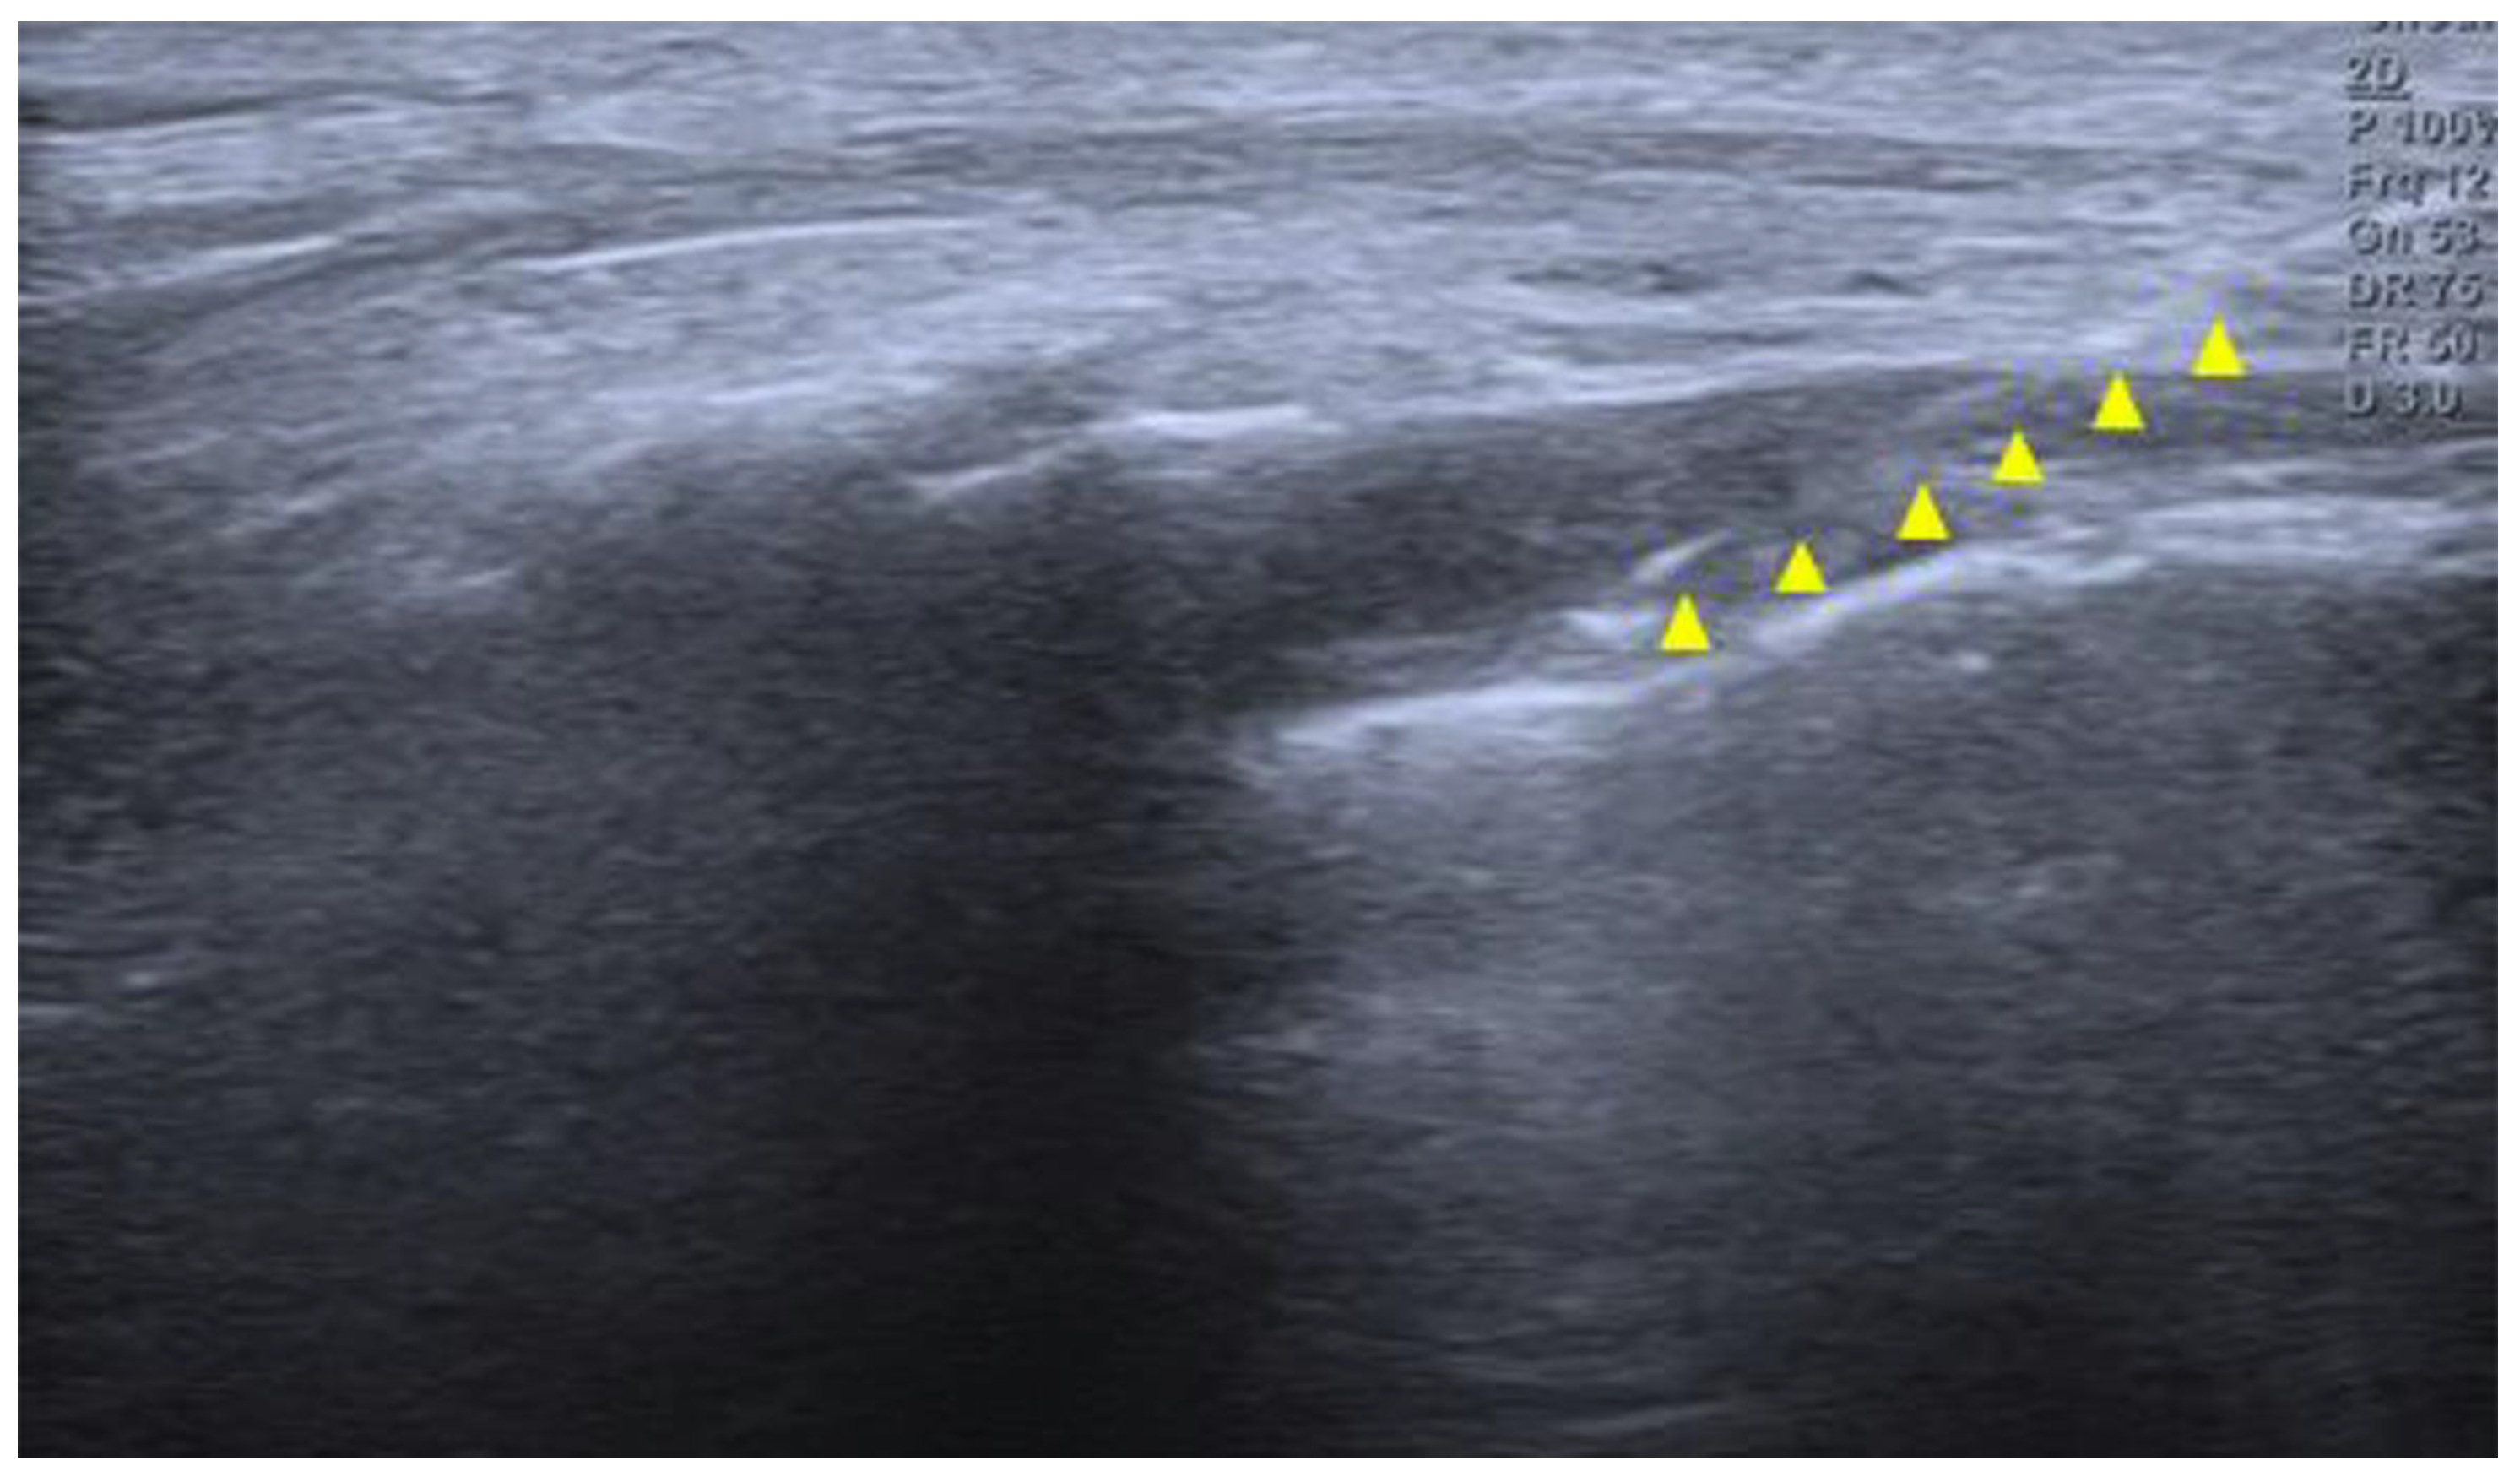

A 14-year-old girl developed coccygeal pain following a fall inside a bus six months earlier. At that time, she was diagnosed with sacrococcygeal dislocation at an outside hospital and was prescribed acetaminophen and NSAIDs, which maintained her symptoms at a Numerical Rating Scale (NRS) score of approximately 3. However, one month prior to presentation, she sustained a second fall to the same area, after which her pain worsened despite continued pharmacologic treatment, reaching an NRS score of 6. She was therefore referred to our pain clinic. The radiographs obtained at the time of the initial injury were unavailable. Radiography performed at our institution demonstrated anterior angulation of the coccyx (Figure 1). Physical examination revealed tenderness over the sacrum and coccyx. The patient was able to sit but could not remain seated for prolonged periods due to pain, and reported worsening pain upon standing. No cutaneous abnormalities or swelling were noted over the coccygeal region. She denied defecation-related pain. For pain control, an ultrasound-guided caudal epidural block was performed (Figure 2). Under sterile conditions, the patient was positioned prone, and the sacral hiatus was identified using ultrasound. After local anesthesia of the skin at the needle insertion site, a butterfly catheter was advanced toward the sacral hiatus under an out-of-plane view, traversing the sacrococcygeal ligament. The needle was then redirected in-plane into the epidural space. A mixture of 8 mL of 2% mepivacaine, 1 mL of 0.9% normal saline, and 5 mg of dexamethasone was injected. At the 2-week follow-up, although the qualitative character of pain remained similar, the patient reported an increased ability to remain seated and a reduced frequency of pain when standing. Her pain intensity decreased significantly to an NRS score of 2, accompanied by noticeable functional improvement. At the 2-month follow-up, her pain remained at an NRS score of 2, and she maintained a level of daily functioning without significant limitations.

Figure 2. Ultrasound image of the sacral hiatus during caudal epidural block. The needle is seen advancing through the sacrococcygeal ligament into the caudal epidural space under real-time guidance (yellow triangle).